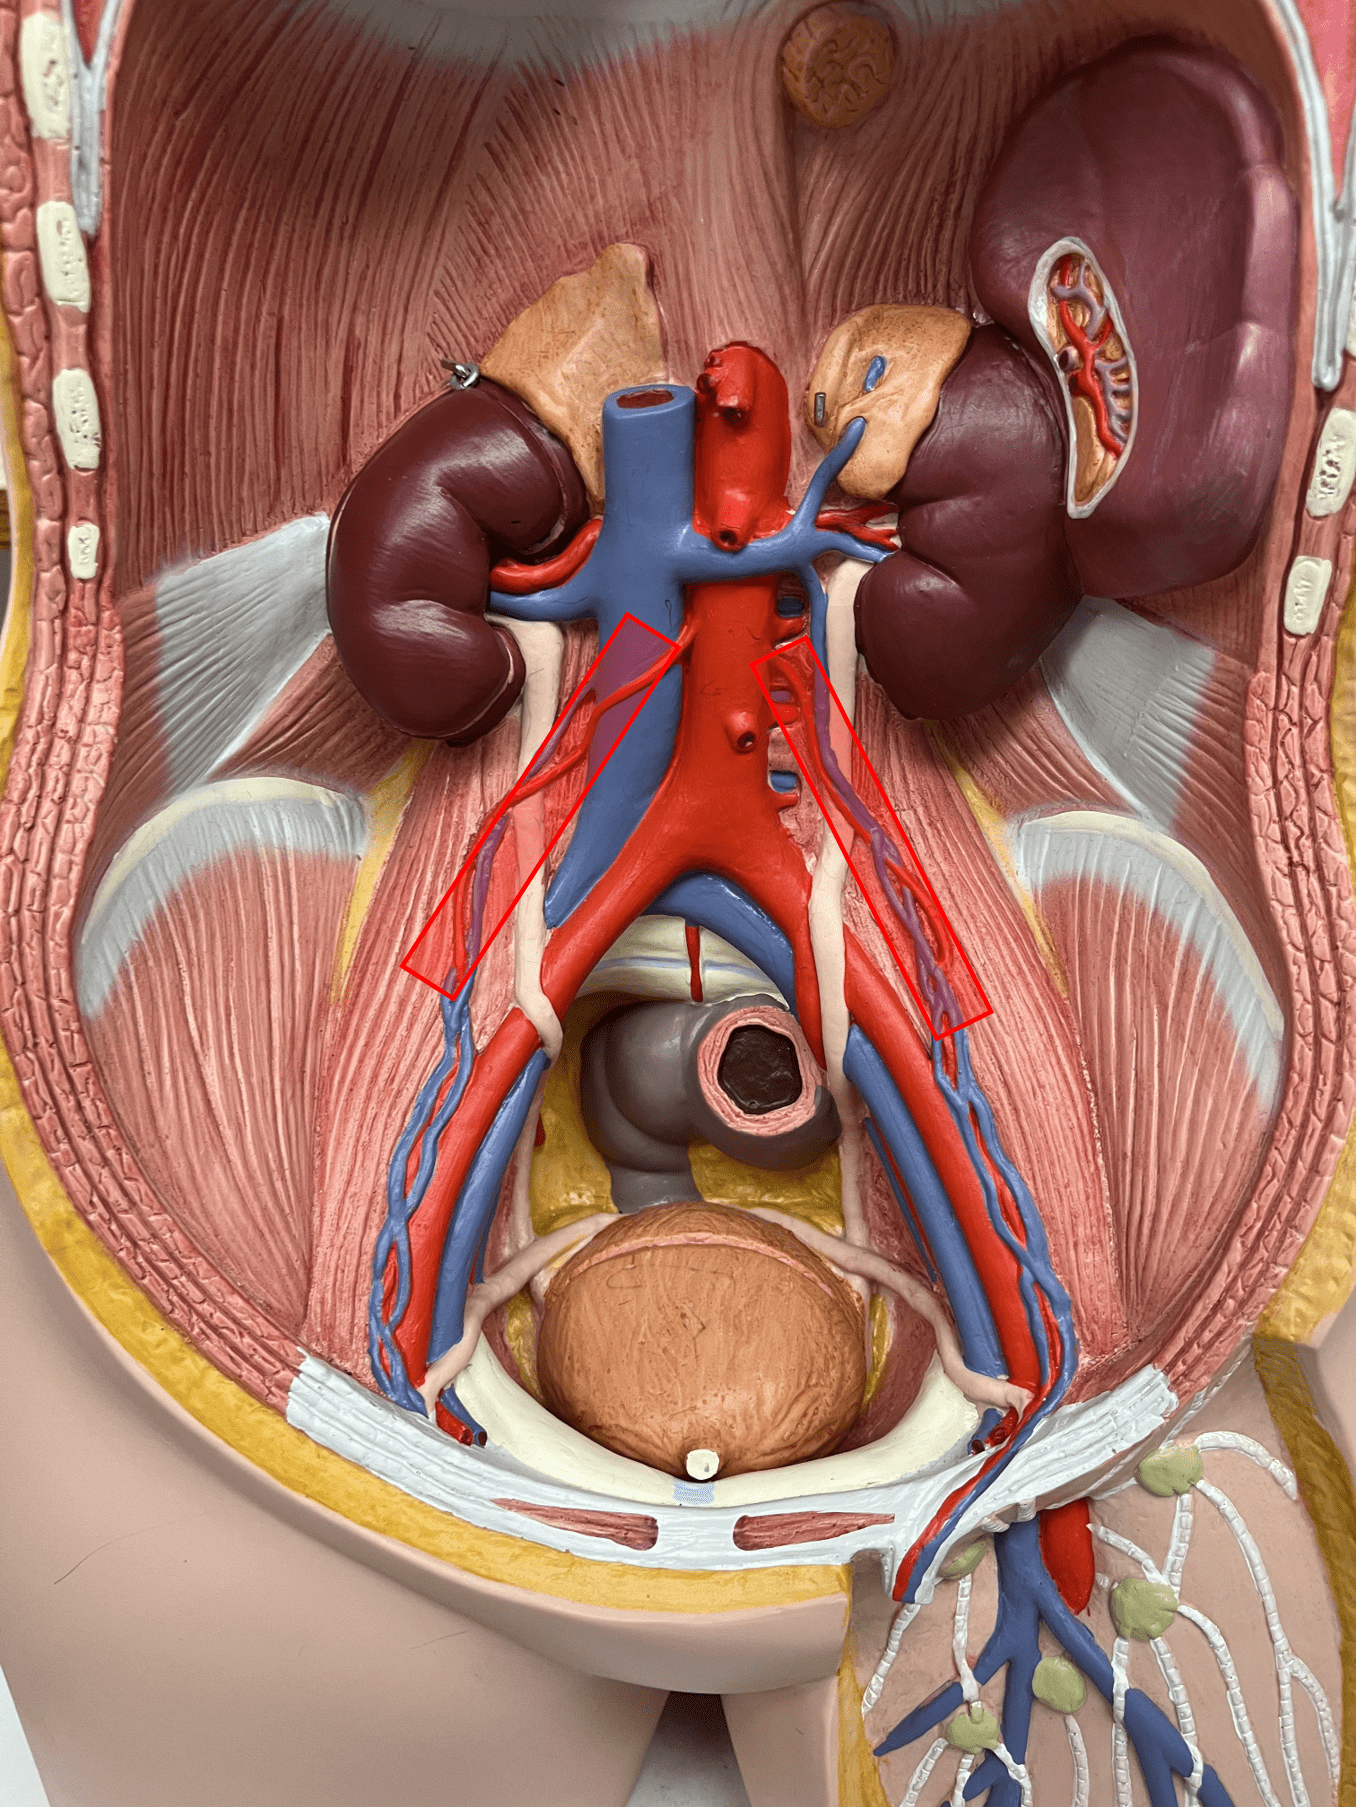

• Found between the tunica externa and tunica media.

11

New cards